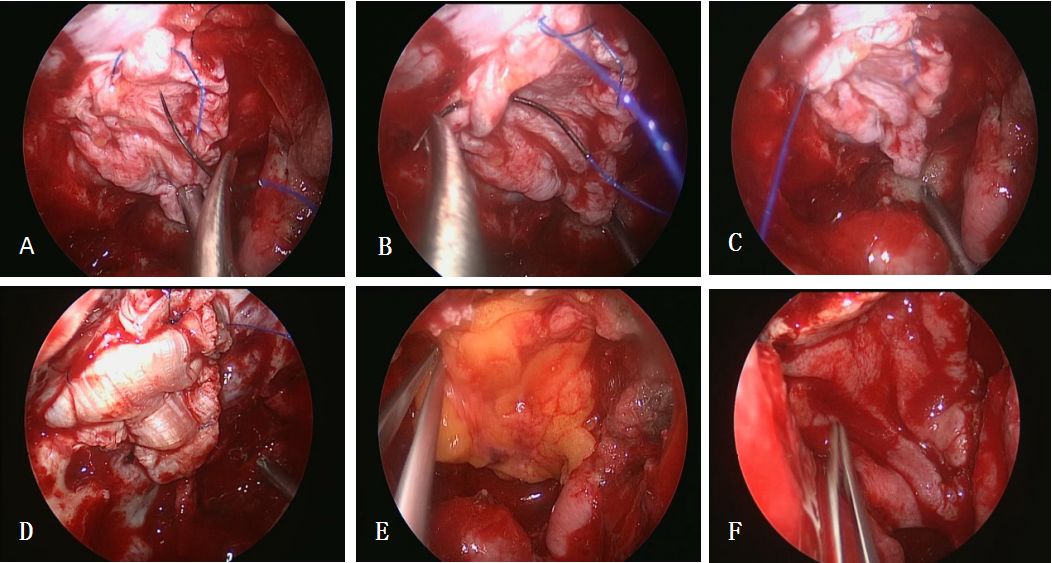

图1. A:肿瘤切除后鞍结节及蝶骨平台颅底硬膜缺损;B:天意福人工硬膜置入硬膜下作为第一层修补材料;C:裁剪合适大小的自体阔筋膜;D:单手缝合右侧颈内动脉远环附近硬膜缘;E:沿缺损硬膜缘逆时针方向连续缝合;F:助手持吸引器配合保障术野清晰,术者单手缝合左侧远环附近硬膜缘。

图2. A、B、C:连续缝合蝶骨平台硬膜缘;D: 自体阔筋膜连续缝合作为第二层修补材料; E: 自体脂肪片贴敷作为第三层修补材料;F: 带蒂鼻中隔粘膜瓣贴敷作为第四层颅底重建材料。